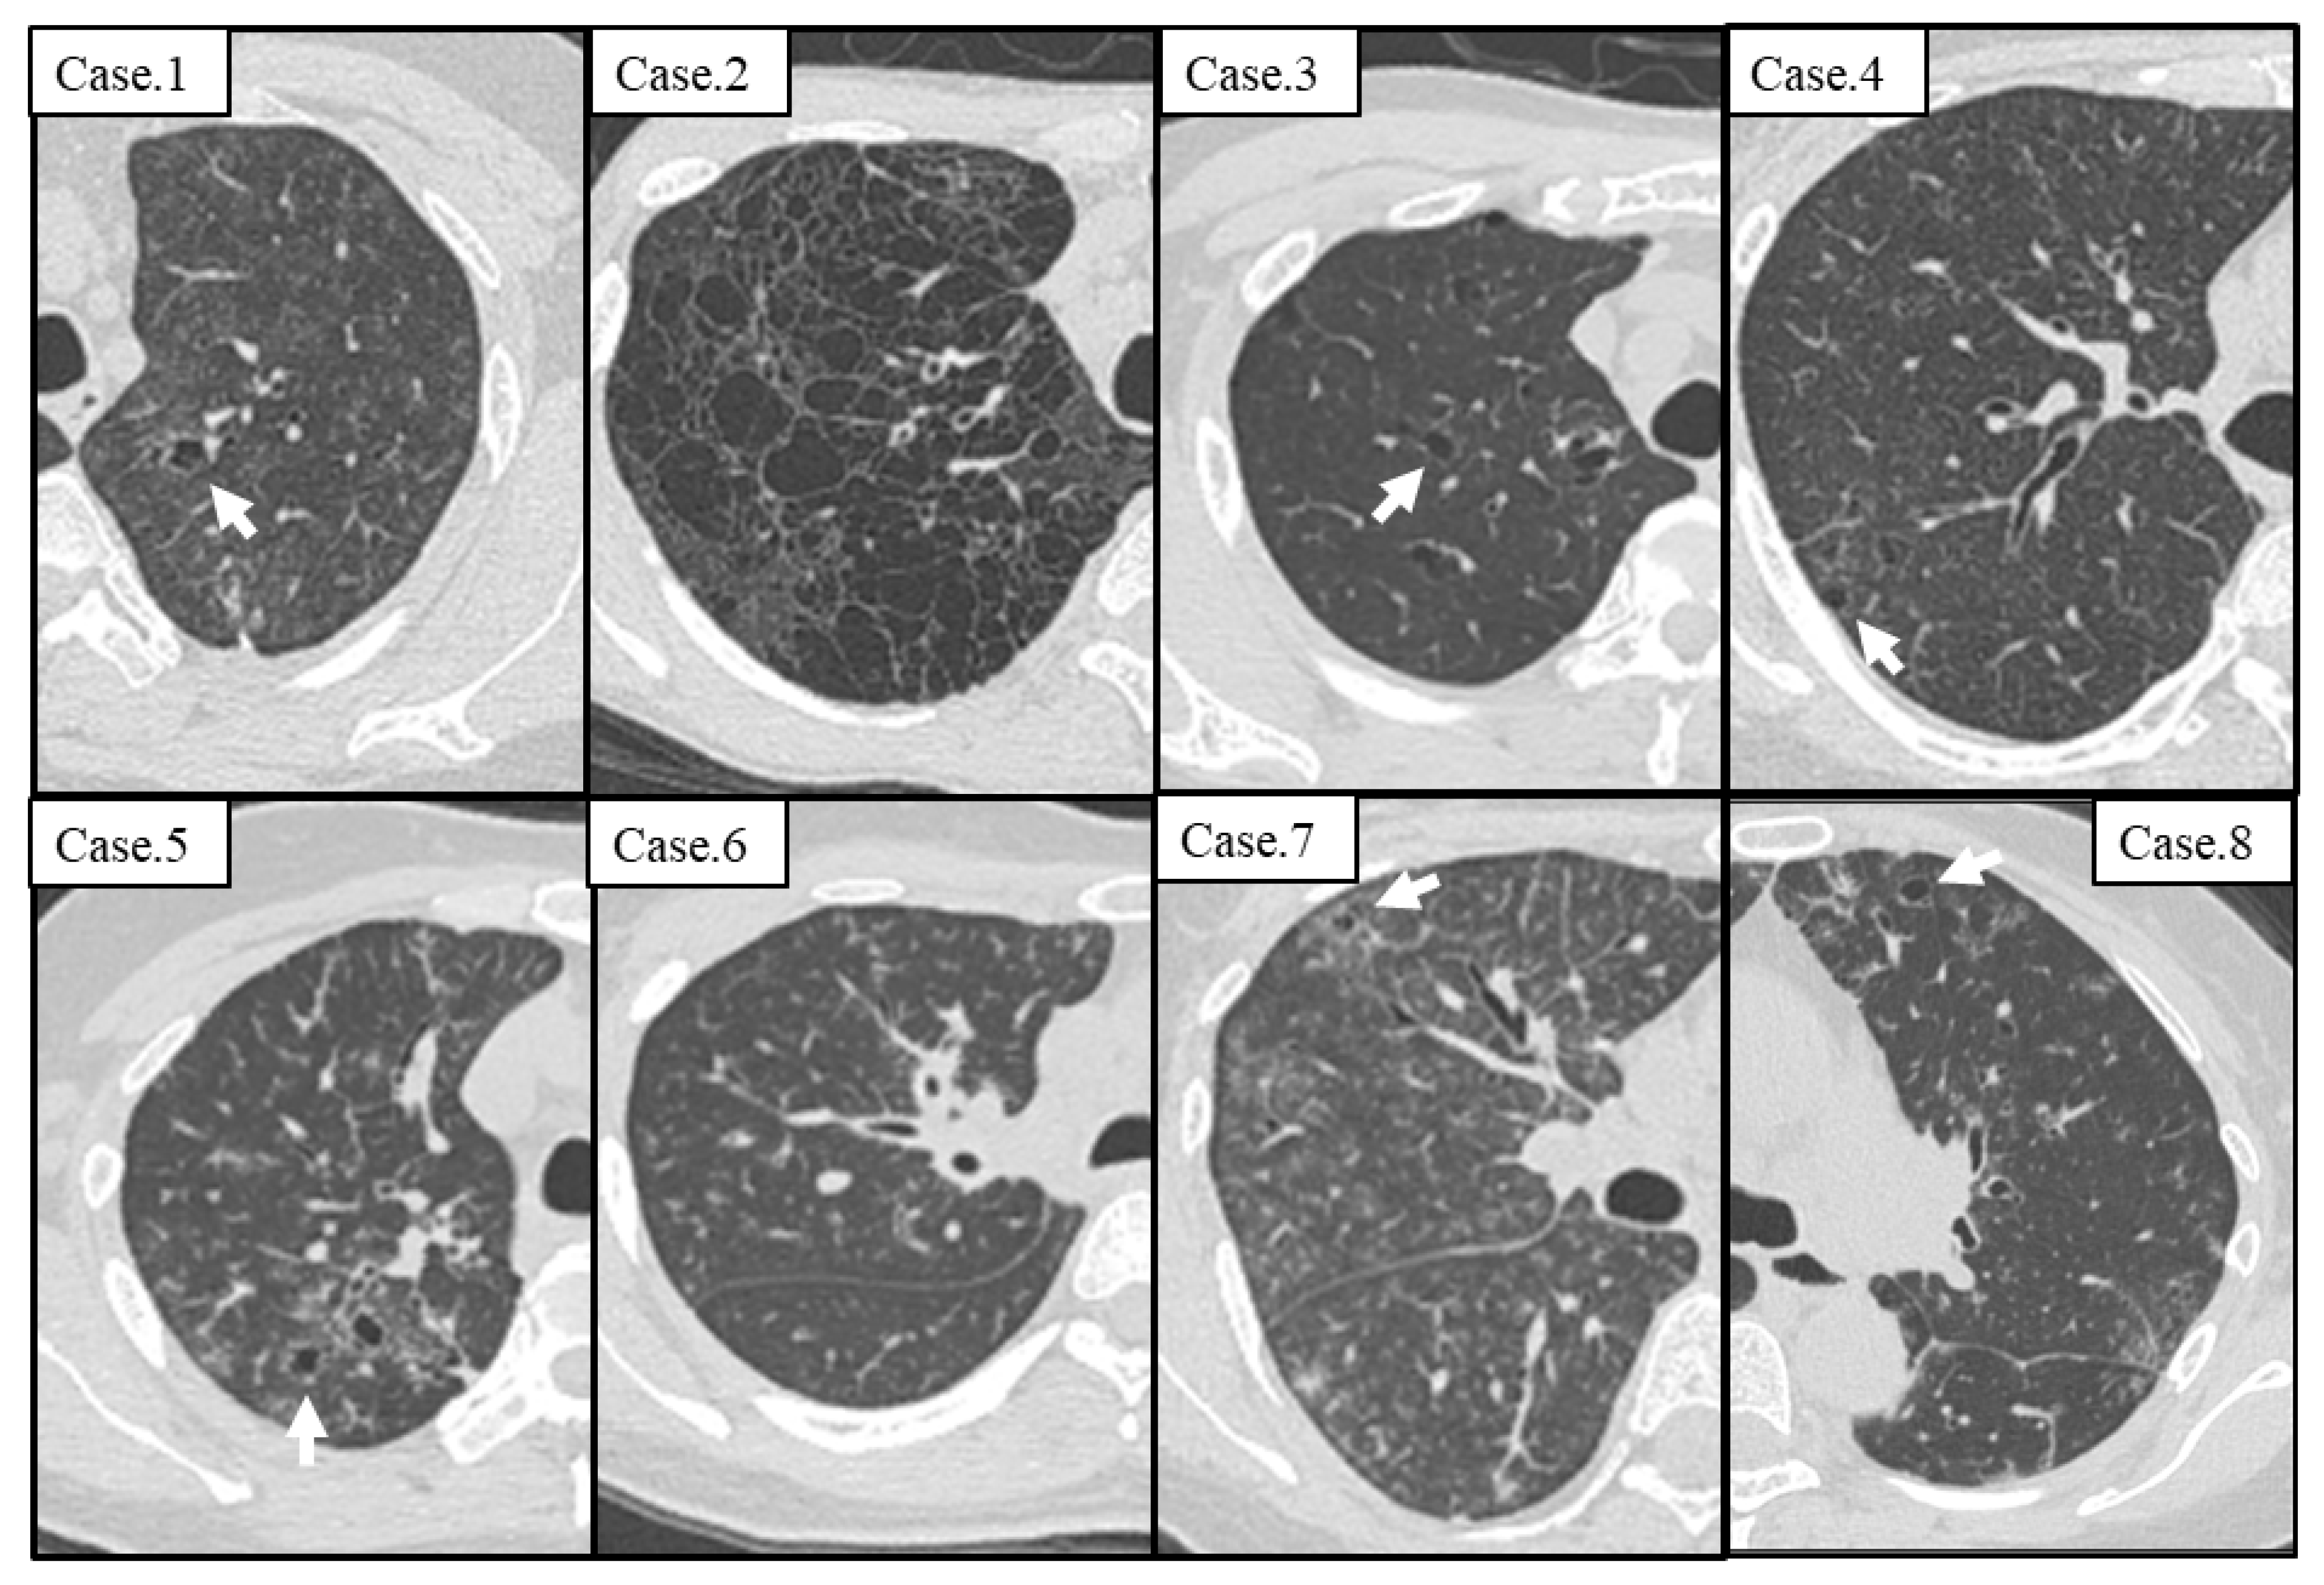

| CT Findings | n = 8 |

|---|---|

| Mediastinal lymphadenopathy | 8 (100%) |

| Interlobular septal thickening | 8 (100%) |

| Centrilobular nodules | 8 (100%) |

| Ground-grass attenuation | 8 (100%) |

| Cyst formation | 7 (87.5%) |

| Thickening of the bronchovascular bundles | 6 (75%) |

| Air trapping (n = 6) | 5 (83.3%) |

| Consolidation | 1 (12.5%) |

| Bronchiectasis | 1 (12.5%) |

| Pleural effusion | 0 (0%) |

| Case | Detail Characteristics of Cyst at First Visit | Clinical Course | |||||||

|---|---|---|---|---|---|---|---|---|---|

| Cyst | Number | Size | Wall | GGA around Cysts | Distribution | Treatment | The Number of Cysts | ||

| Upper /Lower | Subpleural Area /Interstitial Area /Random | ||||||||

| 1 | + | 2 | 8 mm | <2 mm | + | Upper | Interstitial area | TCZ | No change |

| 2 | + | >100 | 3–30 mm | <2 mm | + | Upper | Random | TCZ | No change |

| 3 | + | 25 | 2–10 mm | <2 mm | + | Upper | Interstitial area | TCZ | Increase |

| 4 | + | 12 | 2–8 mm | <2 mm | + | Upper | Interstitial area | PSL + TCZ | Increase |

| 5 | + | 14 | 3–8 mm | <2 mm | + | Upper | Interstitial area | Observation | Increase |

| 6 | − | NE | NE | NE | NE | NE | NE | TCZ | Increase |

| 7 | + | 3 | 2–3 mm | <2 mm | + | Upper | Interstitial area | TCZ | Increase |

| 8 | + | 32 | 3–9 mm | <2 mm | + | Upper | Interstitial area | TCZ | Increase |

| Summary | 7/8 (87.5%) | 1–9; 2 10–99; 4 >100; 1 | <10 mm; 6 >10 mm; 1 | <2 mm; 7 >2 mm; 0 | 7/7 (100%) | Upper; 7 Lower; 0 | Subpleural; 0 Interstitial; 6 Random; 1 | TCZ; 6 PSL + TCZ; 1 Observation; 1 | Increase; 6 No change; 2 Decrease; 0 |